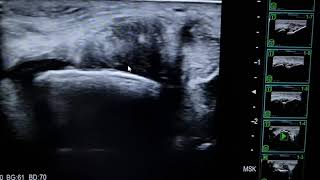

WebSíntomas de ruptura del extensor del extensor del dedo El primer tipo. Hay dolor en el momento de la lesión, luego una hinchazón moderada del dedo y una. WebRotura parcial del tendón extensor común jugador de pádel. 20 febrero, 2019. Gracias a la Ecografía detectamos una rotura parcial del tendón extensor común. WebLos síntomas habituales de una lesión en la articulación del codo y sus estructuras circundantes incluyen hinchazón y dolor, que pueden extenderse desde el codo hasta el. WebEl tendón del manguito rotador es una de las áreas más comunes del cuerpo afectadas por la lesión del tendón. Algunos estudios de autopsia han demostrado que 8% -20%. WebLesión del tendón extensor del dedo de la mano. Lesión, rotura tendón de la mano ¿Qué pasa si se me rompe el tendon del dedo? En este vídeo hablamos esta le... WebLa ruptura del tendón extensor común es la lesión del tendón agudo más común del codo. Los autores describen un caso de un paciente con antecedentes clínicos de. WebEn la articulación del hombro: La ruptura proximal del tendón del bíceps es una lesión del tendón del bíceps que se produce en la articulación del hombro. Es el tipo más. WebLa epicondilitis medial también conocida como codo del golfista es una lesión inflamatoria que afecta al tendón flexor común del codo. Es menos frecuente que la epicondilitis.

WebSientes un dolor que parte del codo y se irradia a todo el antebrazo. Sientes dolor al tocar la parte externa o interna del codo. Tienes dolor al extender el brazo. La rotación del. WebLa ruptura del tendón extensor común es la lesión del tendón agudo más común del codo. Los autores describen un caso de un paciente con antecedentes. WebLa interrupción del aparato extensor es una lesión muy discapacitante que debe diagnosticarse de inmediato. El dolor es de comienzo brusco, con edema y pérdida de.